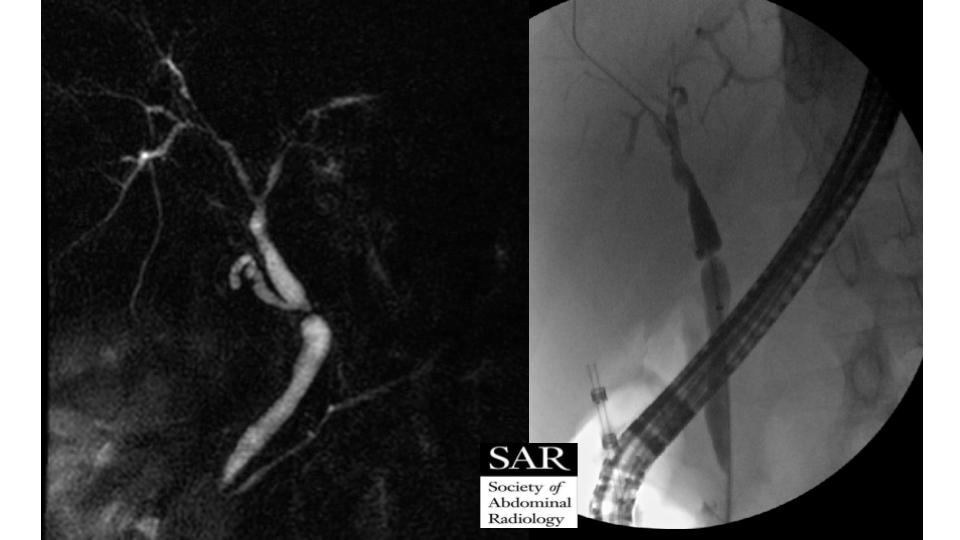

This week's case is a biliary anastomotic stricture post liver transplant. Congrats on the right answers!pic.twitter.com/Ncdbb8vkjO

This liver transplant patient is our gettable case of the week - we need your diagnosis below!pic.twitter.com/5lM8c0TBc4